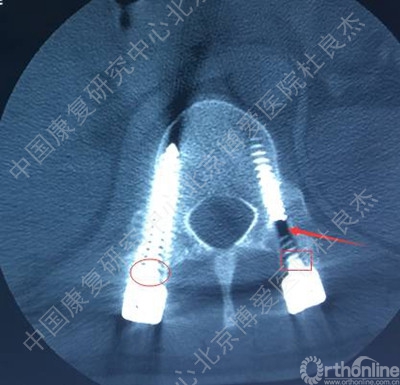

3、胸12椎弓根钉断裂

柳申鹏 #1胸腰段椎体骨折脱位出现断钉原因:1.此处骨折脱位除椎体骨折外,附件及韧带等软组织损伤严重。从解刨上看3种因素决定此处是应力集中地。需固定到伤椎上下各2个椎体。2.从影像学可知,胸12腰1似乎过度撑开了。3.从影像学可知,极度不稳,应融合胸12腰1。下一步:去除断钉,延长上方固定到胸10或11并做后路截骨椎间隙植骨。或前路椎间隙植骨融合内固定